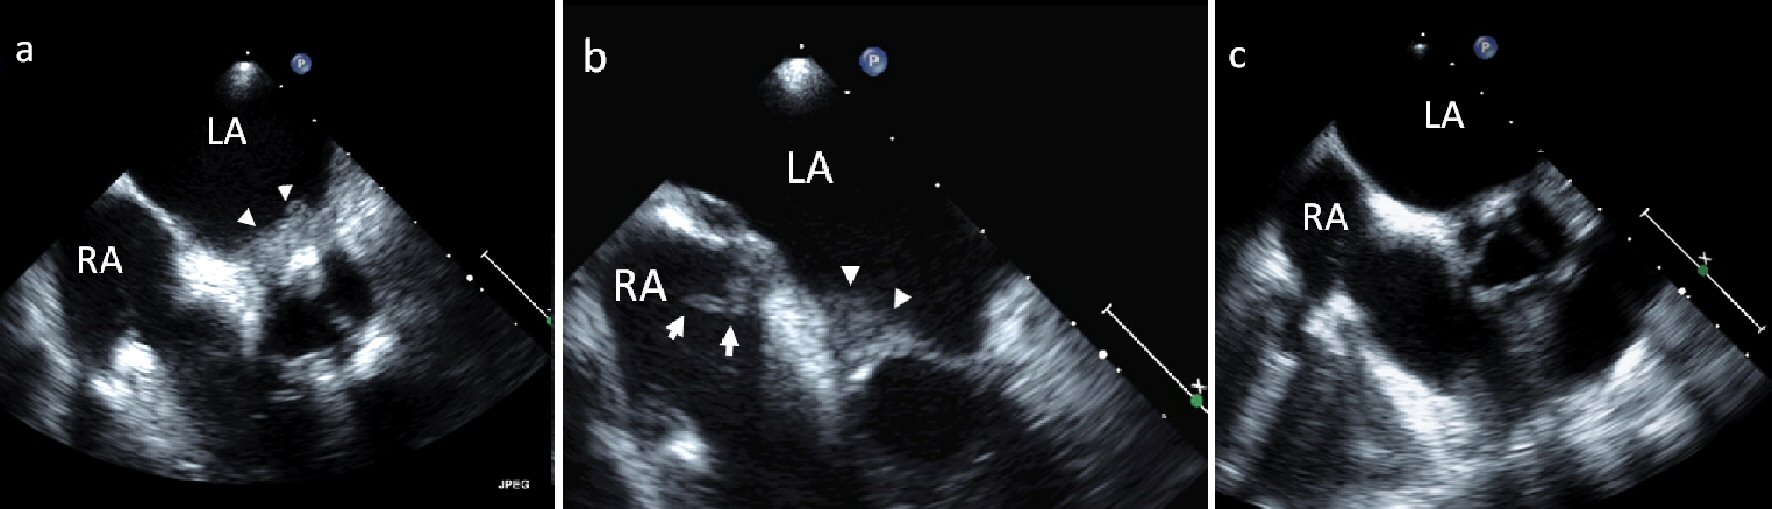

A 63-year-old woman with breast cancer status post lumpectomy and radiation, rheumatoid arthritis, and paroxysmal atrial fibrillation, presented with diplopia and was found to have multiple embolic strokes. She had multiple flares of her rheumatoid arthritis in the past, including an inflammatory pericardial effusion, but it was currently in remission on methotrexate and certolizumab. Brain magnetic resonance imaging (MRI) revealed thalamic and cerebellar infarcts. Transesophageal echocardiography (TEE) demonstrated sessile masses in the left atrium (LA) and right atrium (RA) that were contiguous with the interatrial septum, as well as a pedunculated mass in RA (Fig. 1a, b) (Supplementary Videos 1a, b) (www. cardiologyres.org). Cardiac MRI confirmed biatrial masses with a heterogenous enhancement pattern suggesting vascularization, most consistent with an inflammatory or neoplastic process and not a thrombus. Surgical resection was not felt to be feasible because of the multiple locations of these lesions, which suggested a systemic process. She was started on warfarin (goal INR 2 - 3) with a heparin bridge given a history of paroxysmal atrial fibrillation with multiple embolic strokes, treated with prednisone for rheumatoid arthritis-related tenosynovitis, and her methotrexate was stopped. Repeat TEE 2 months later revealed near-complete resolution of the atrial masses (Fig. 1c). Cardiac MRI 2 years later showed a mobile avascular echodensity in the RA most consistent with thrombus (different from prior study). She was lost to follow-up so it is unknown if she was still on warfarin at that time.

![]() Click for large image | Figure 1. (a, b) TEE of sessile masses in the LA and RA (arrow heads) as well as a pedunculated mass in the RA (arrow with tail) in a patient with rheumatoid arthritis. (c) TEE 2 months after initiation of warfarin, prednisone, and cessation of methotrexate shows near-complete resolution of the atrial masses. |